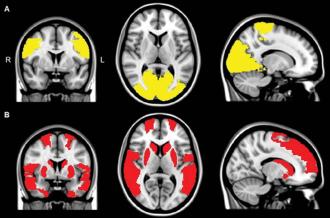

Imagens em ressonância mostram atividade reduzida em pacientes com Parkinson (amarelo) e em pacientes com Parkinson e alucinações (vermelho). Conexões funcionais foram significativamente mais baixas em pacientes que relataram alucinações. Créditos: Radiological Society of North America

Os resultados mostraram que em todos os pacientes com Parkinson múltiplas regiões do cérebro comunicavam-se menos com as demais, em comparação com o resto do grupo de controle. Contudo, em pacientes que sofreram de alucinações visuais, várias áreas adicionais mostraram conectividades em déficit com o resto do cérebro. Especialmente, aquelas pertinentes à atenção e processos de informações visuais.

“Descobrimos que nestas áreas onde desenvolve-se a atenção e processos visuais falta comunicação com o resto do órgão”, disse o autor do estudo Menno M. Schoonheim, Ph.D. do Departamento de Anatomia e Neurociências da VUMC. “Isso sugere que o desligamento entre estas regiões podem contribuir para os dados sintomas entre os pacientes de Parkinson.”.